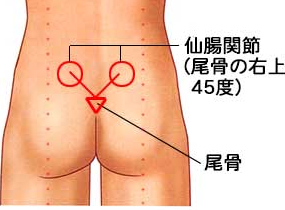

◯仙骨部〜仙腸関節部などの骨盤後方部を含めた圧痛や叩打痛の有無

仙腸関節の場所を正確に…↓(イラスト参照:腰痛と仙腸関節の関係 〜 関節の異常が痛みの原因?)